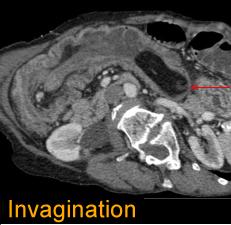

.Complication d'

invagination d'une lipome a grande taille ( fleche

rouge ) . |

Aspect TDM invagination par une

lipome de l'intestin ( coupe frontale ) |